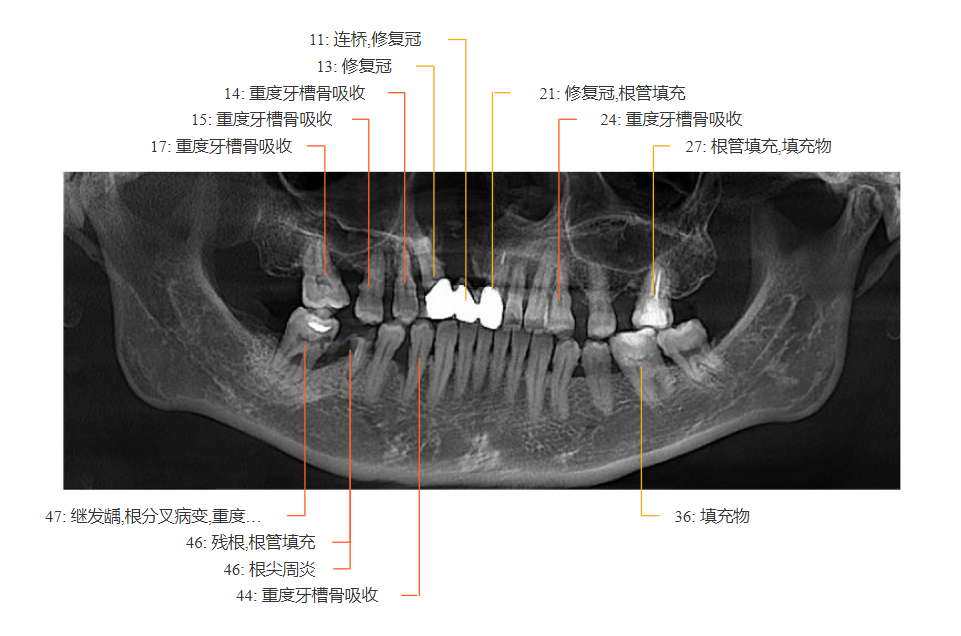

倪女士治疗前CT片检查:

全口牙槽骨:不同程度吸收

牙缺失:12、16、26

继发龋+根分叉病变:47

残根+根尖周炎:46

牙结石:全口牙齿

牙龈红肿得厉害,轻轻一碰就出血;牙齿上堆满了黄黑色的牙结石,说话时都能看到;更严重的是,不少牙齿周围的“缝隙”(医学术语:牙周袋)深到10毫米——要知道,健康的牙周袋最多3毫米,超过这个数,就像城墙地基被蛀空,牙齿早晚会松动脱落。

口腔CT片更直观地暴露了问题:支撑牙齿的骨头(牙槽骨)几乎被“啃”掉了三分之二,最薄的地方仅1.59mm......

患者术前牙槽骨最“薄”处仅1.59mm